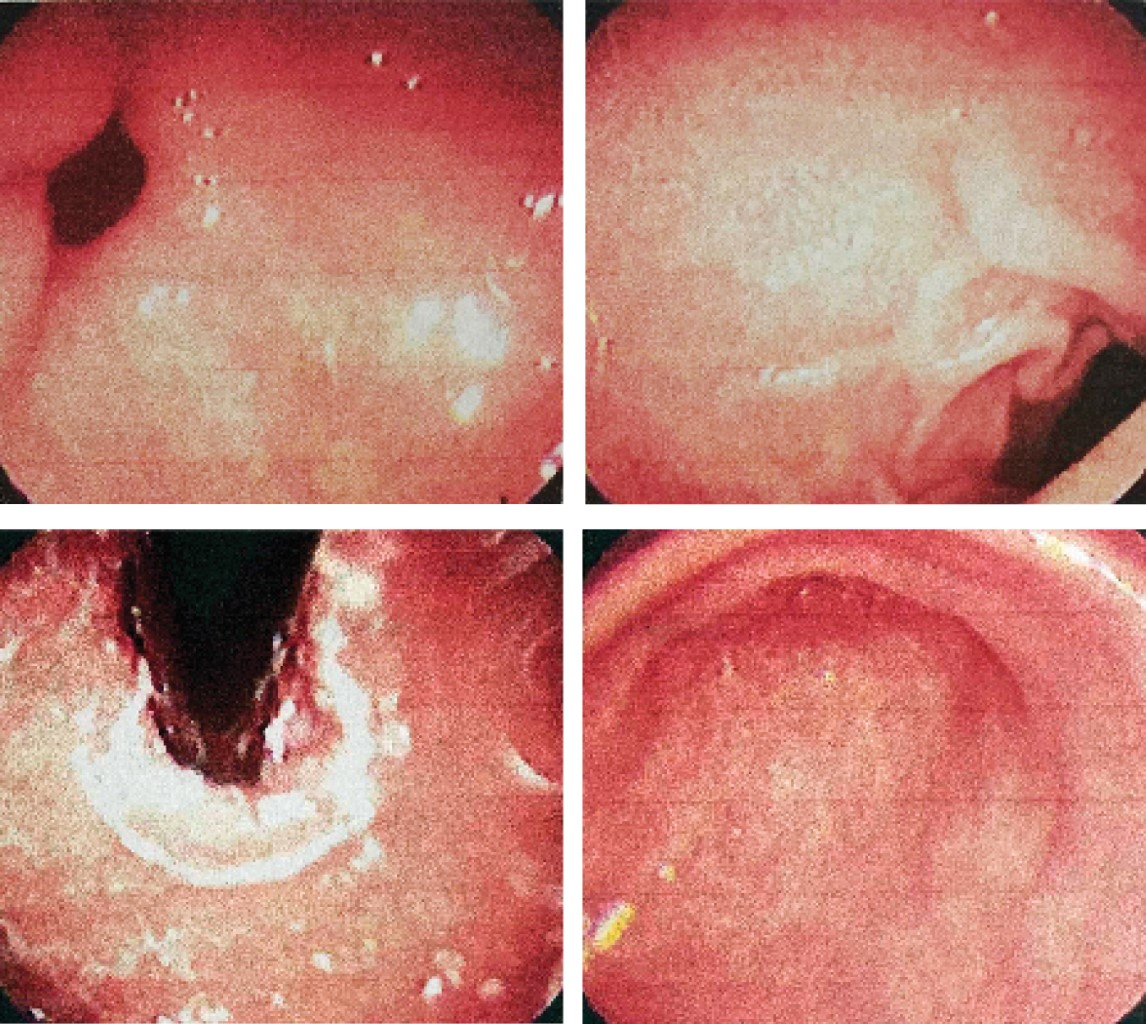

A 66-year-old female patient with no significant personal history manifests pain in the epigastrium, burning type, with retrosternal irradiation, regurgitations, and heartburn, symptoms that improve with the use of proton pump inhibitor and sucralfate; this treatment has been taken chronically, with events of remissions and exacerbations, so a study protocol is initiated on suspicion of gastroesophageal reflux. Endoscopy was requested, which reported probable esophageal dysmotility type A of achalasia and mild antral gastritis (Figure 1). With this result, an imaging contrast study and manometry were requested.

Figure 1